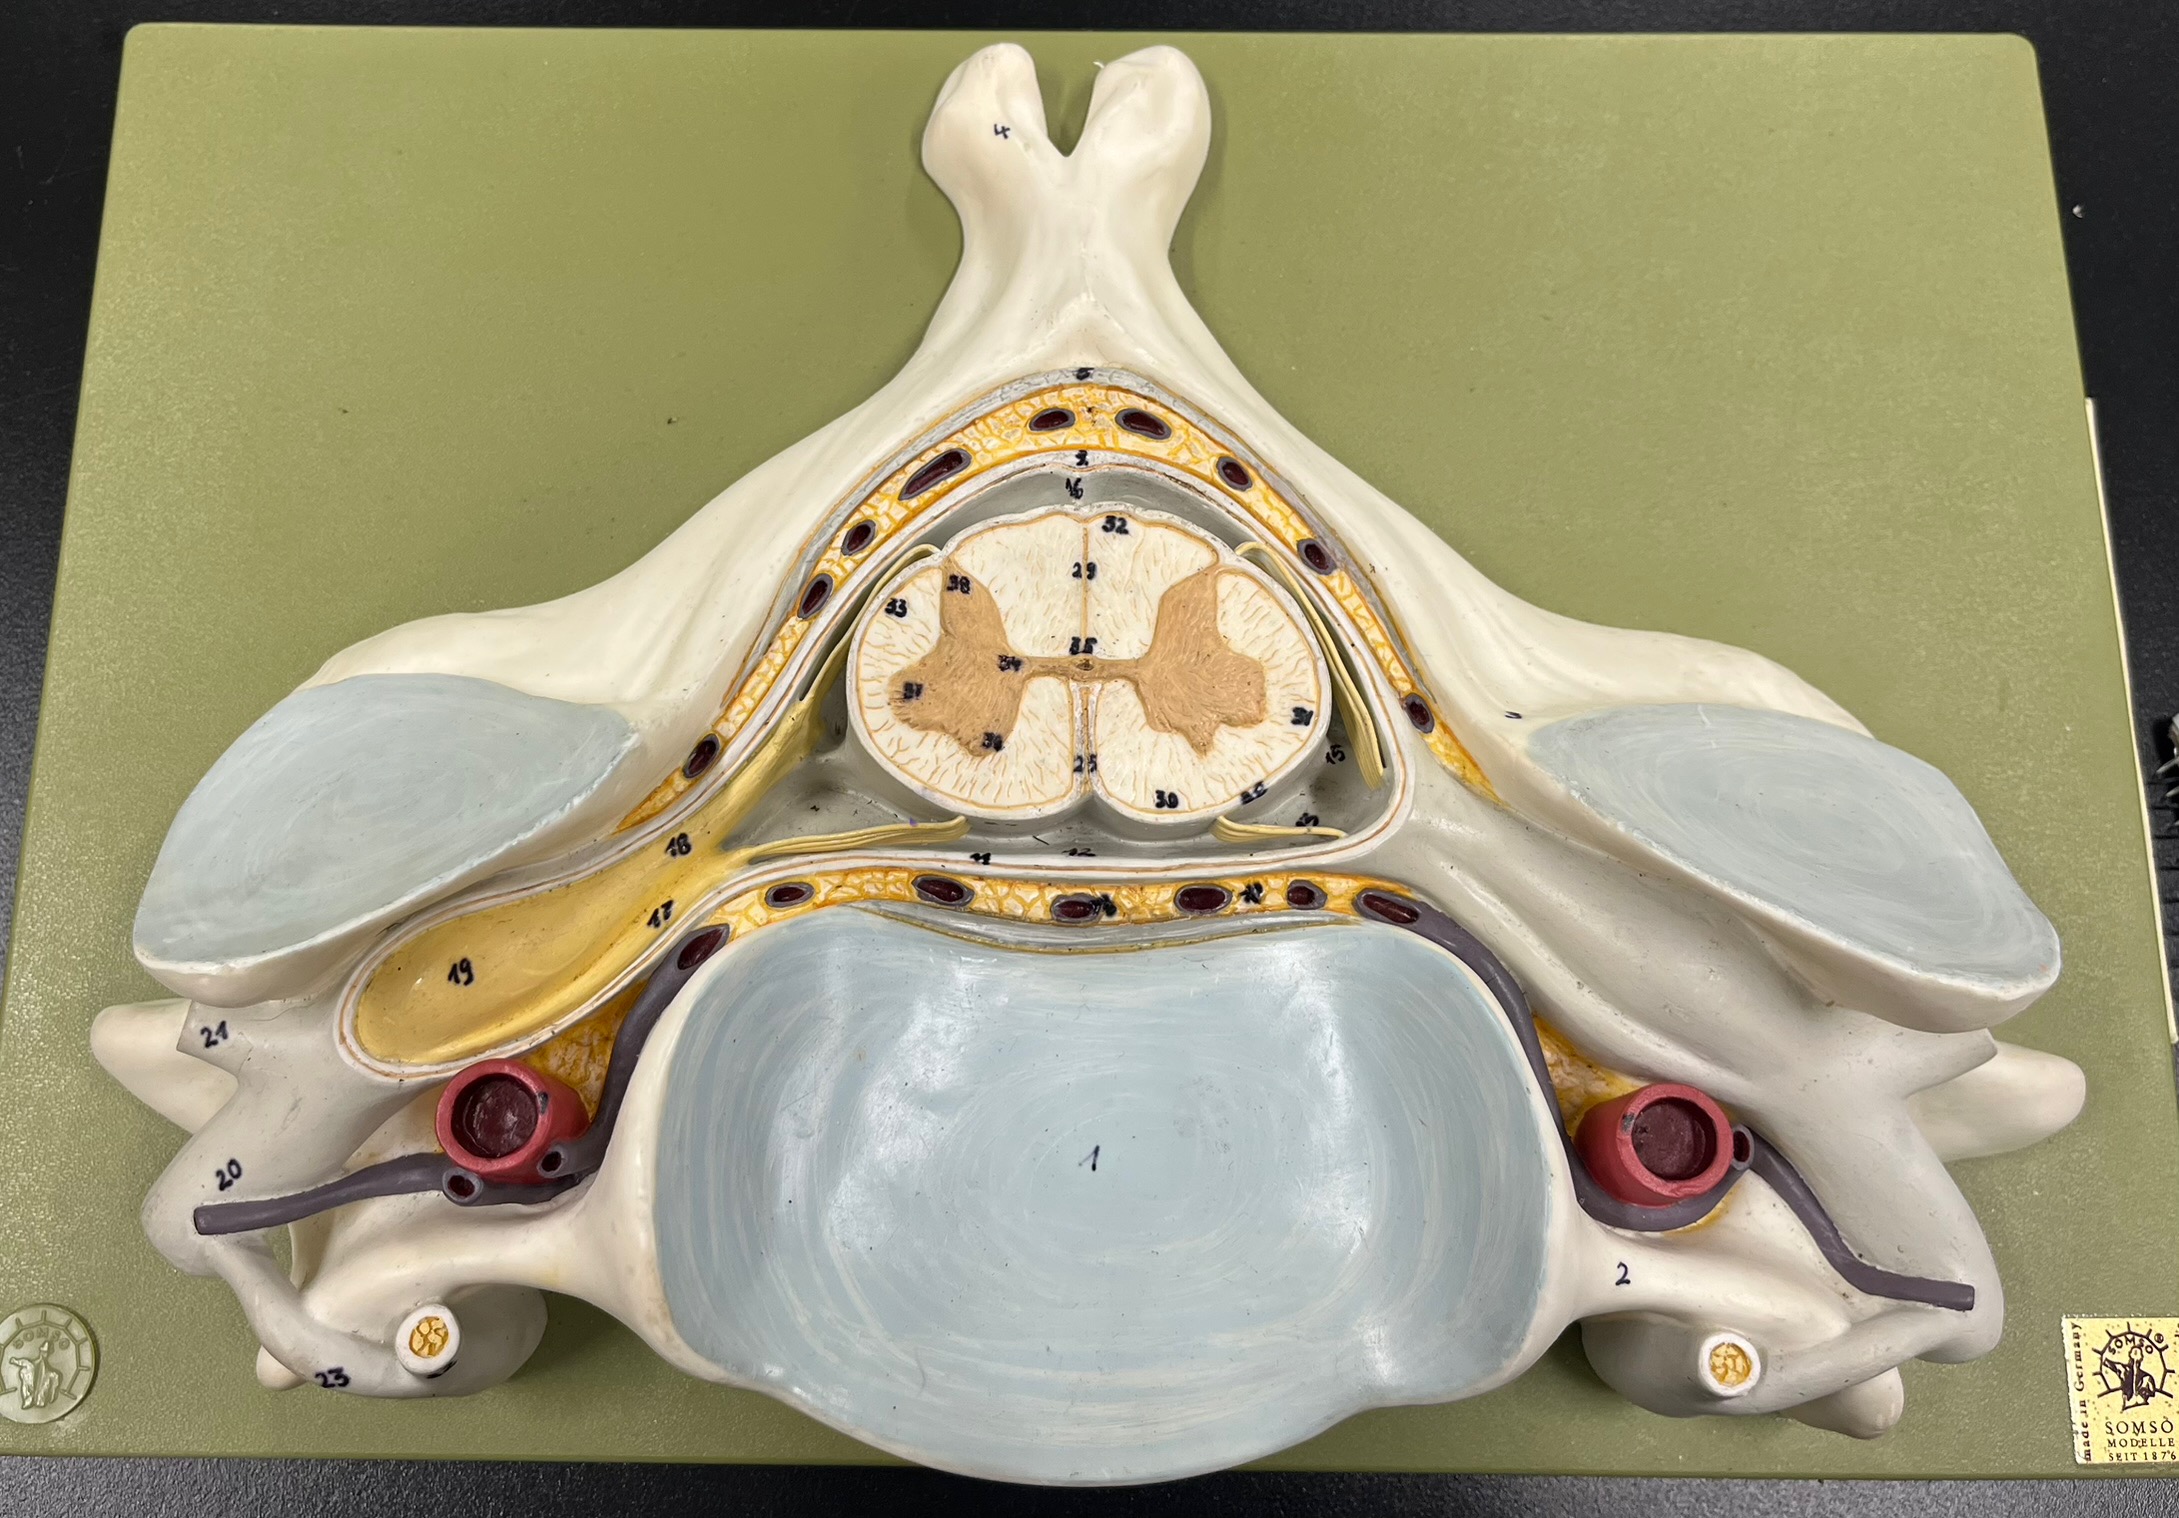

epidural space

dura mater

subdural space

arachnoid mater

subarachnoid space

pia mater

denticulate ligaments

What is the groove here?

anterior median fissure

posterior median sulcus

posterior (dorsal) horn

posterior (dorsal) horn; R—>L

anterior (ventral) horn

lateral horn (selected models)

gray commissure

central canal

anterior column

lateral column

posterior column

white commissure

posterior (dorsal) root ganglion

What is the bulb here?

posterior (dorsal) root ganglion

posterior (dorsal) root

posterior (dorsal) root

anterior (ventral) root

anterior (ventral) root

dorsal ramus

dorsal ramus

ventral ramus

ventral ramus

rami communicantes

rami communicantes

sympathetic chain ganglia

sympathetic chain ganglia